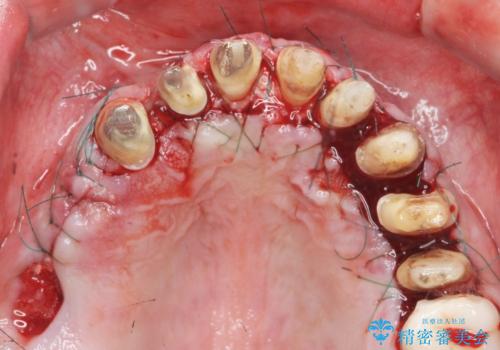

歯周組織検査を行うと歯ぐきからは容易に出血し、X線検査より歯とセラミッククラウンの適合が悪い(ピッタリと合っていない)状態が示唆され、歯ぐきの炎症を惹起している状態でした。

セラミッククラウンを除去し仮歯を装着し、歯周外科手術を行い歯ぐきの状態を改善したのち、適合の良いセラミッククラウンを再作製をする治療計画としました。